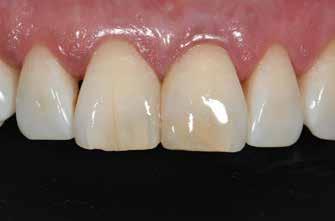

Nem volt kedvencem, de kevésbé kedveltem a hibrid technikát, ahol a palatális fal wax-uppal történő felépítése, majd a nyaki terület szabadkézi megerősítése után a restauráció többi részét mátrixszal lehetett kivitelezni (1. ábra). Bár a kezemben ez valahogy hatékony volt, mégis bonyolult volt.

1. ábra: A wax-up alapú technikák gyakori problémái, a szájpadlásfal apikális része hibás.

2-4. ábra: Gyakori problémák klasszikus megközelítéssel. 5. ábra: Tökéletes vészhelyzeti profil elülső szárnyas technikával. Dr. Jun Iwata, Japán jóvoltából.